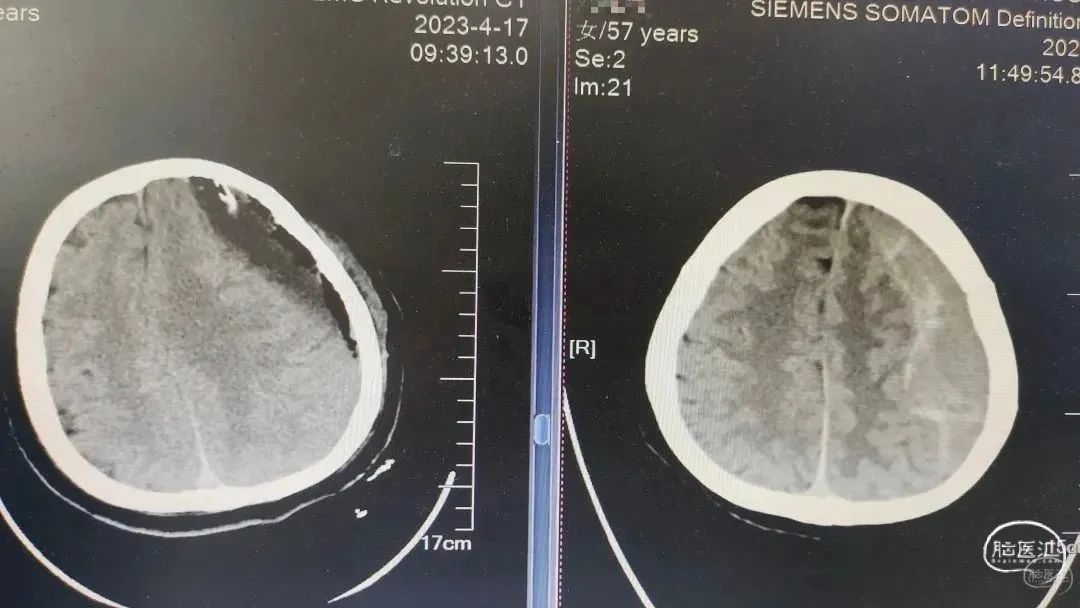

术前CT

术前术后对比